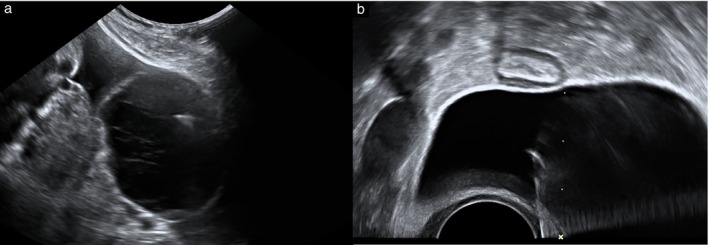

Results: Overall, 46 patients underwent ultrasound-guided cyst aspiration for the management of adnexal torsion, 24 (52%) of whom were pregnant. At ultrasound examination, all 46 cysts had unilocular morphology, and in 96% (44/46) of cases, the cyst content was anechoic. Cyst aspiration was performed transabdominally in 30 (65%) patients and transvaginally in 16 (35%) patients. A total of 39 (85%) patients experienced complete resolution of symptoms immediately after ultrasound-guided cyst aspiration. One procedure was abandoned owing to patient discomfort and six (13%) patients reported non-resolution or short-term recurrence of symptoms, necessitating emergency laparoscopy in seven patients. No complications occurred as a result of ultrasound-guided cyst aspiration. Three patients had cyst aspiration more than once. Follow-up data were available for 29/39 (74%) patients who had successful ultrasound-guided cyst aspiration and received a subsequent ultrasound assessment in our clinic. In 8/29 (28%) patients, the cyst had completely resolved. In total, 4/21 (19%) patients with a persistent cyst opted for elective surgical intervention, while 17/21 (81%) continued conservative management at the last follow-up. Overall, 25/29 (86%) of those followed up after successful ultrasound-guided cyst aspiration, and at least 25/46 (54%) of all patients, avoided any form of surgical treatment.

Conclusions: Ultrasound-guided cyst aspiration is an effective treatment for the management of acute adnexal torsion due to a cyst with unilocular morphology and anechoic or hypoechoic fluid content. With the use of this technique, emergency hospital admission and surgery were avoided in the majority of patients. © 2025 The Author(s). Ultrasound in Obstetrics & Gynecology published by John Wiley & Sons Ltd on behalf of International Society of Ultrasound in Obstetrics and Gynecology.